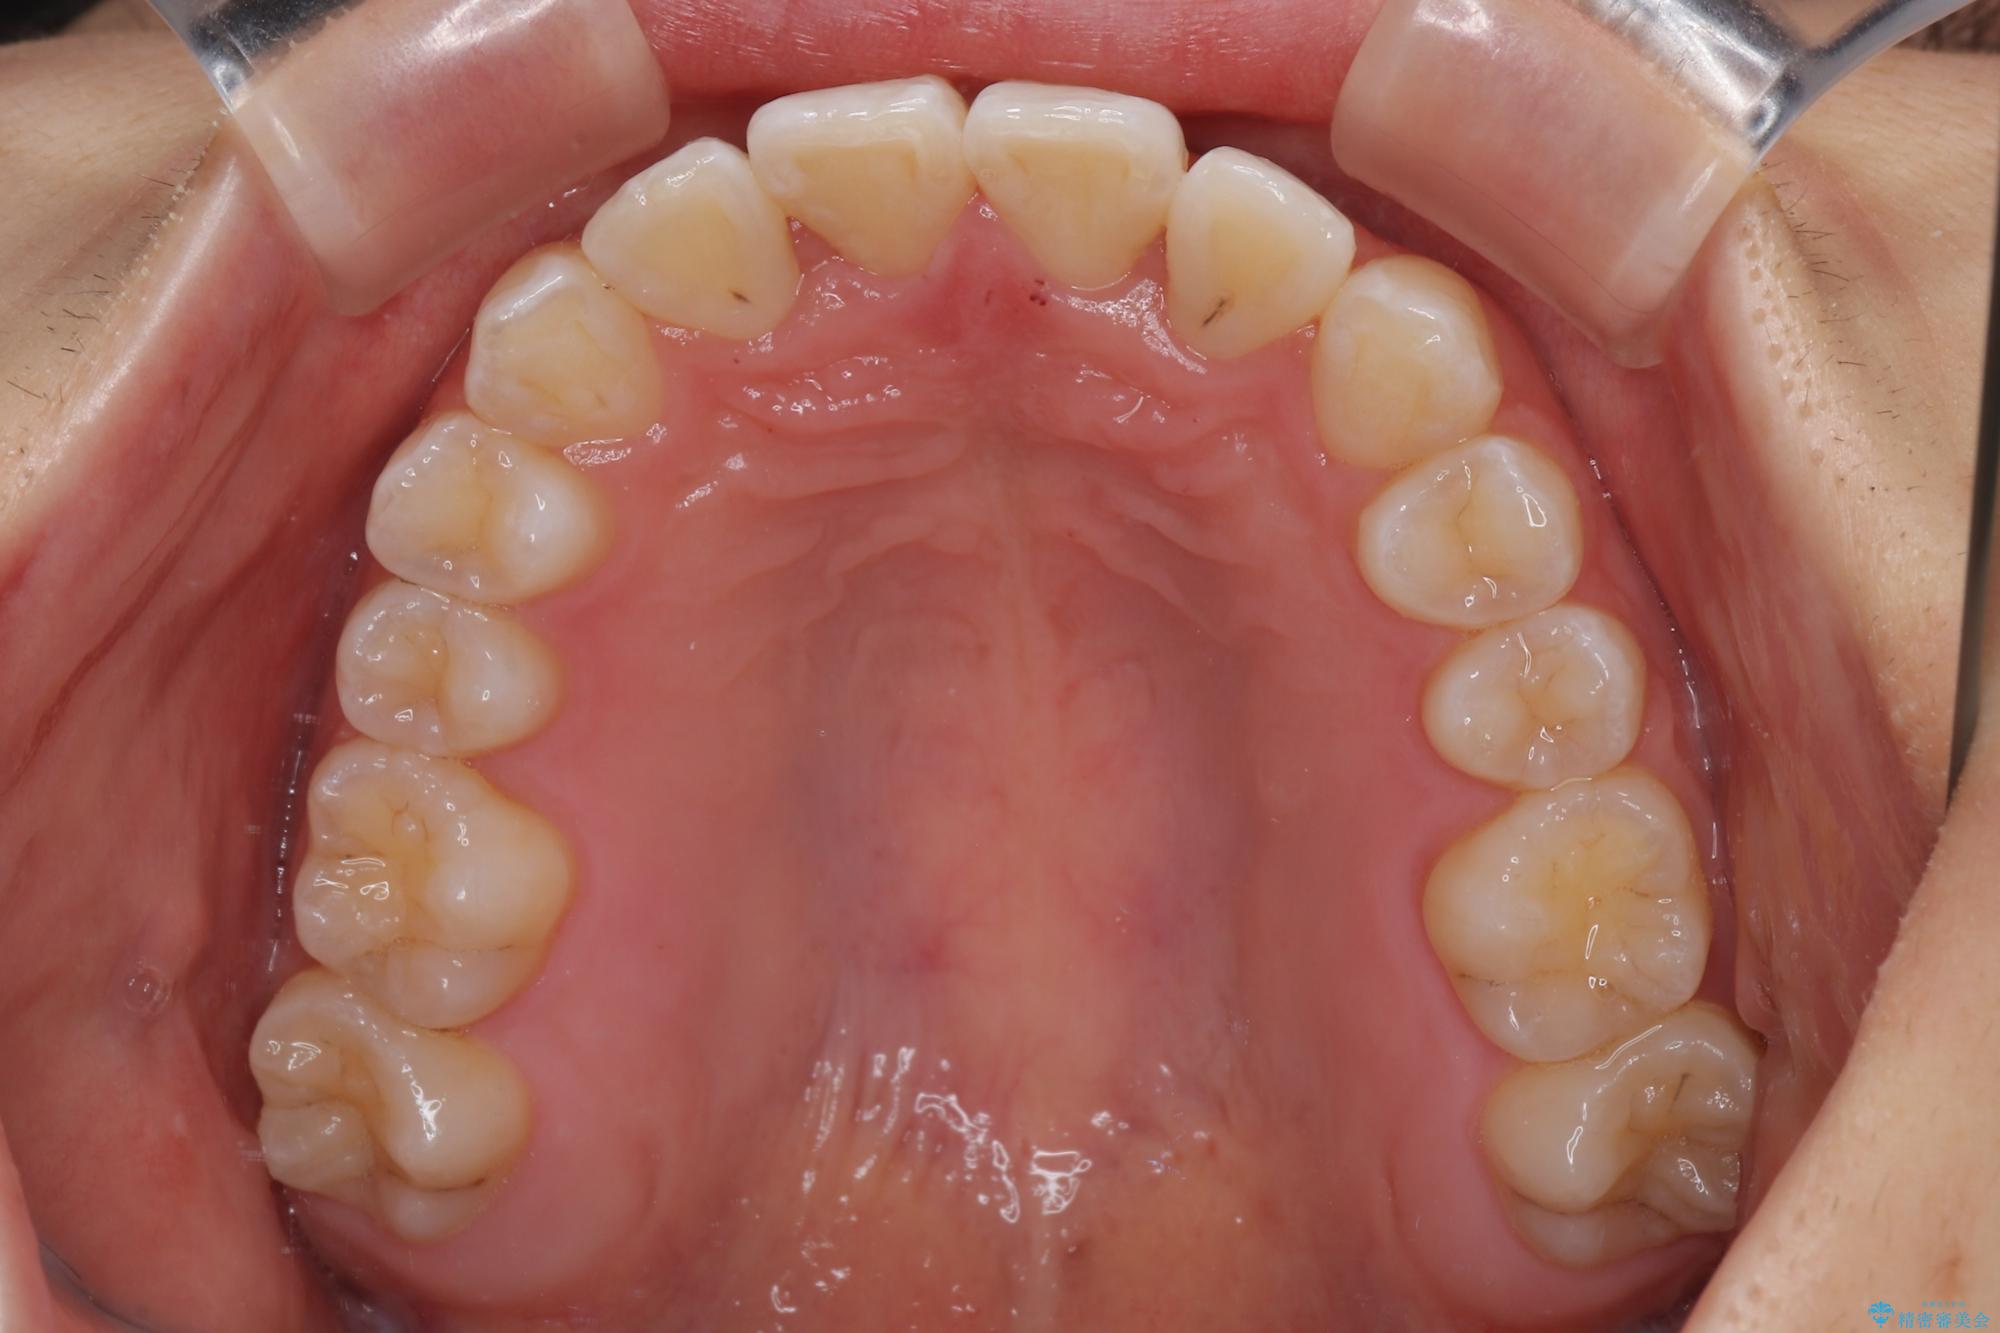

- 上顎前歯のクロスバイトを気にして来院された患者様です。

ワイヤー矯正でもマウスピース矯正でも対応可能でしたが、マウスピースによる自己管理に一切の自信がないとのことで、ワイヤー装置にて矯正治療を行うこととしました。

装置の外見を気にしていましたが、短期間で治療を終えることができるだろうと伝えると、安価であるメタルブラケットを選択されました。

想定通り、1年強で綺麗に仕上げることができました。